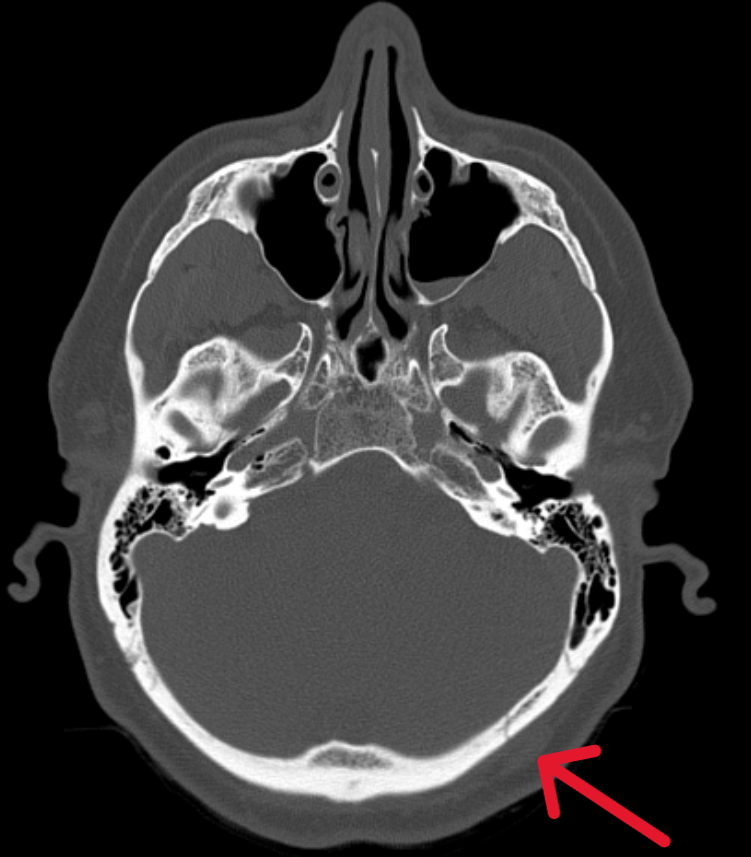

Пациент обратился в Ильинскую больницу, где была проведена компьютерная томография головного мозга и выявлены следующие изменения:

• перелом затылочной кости слева (то место, куда пришелся удар при падении);

• ушиб (контузия) мозга с геморрагическими включениями в правой лобной доле (противоположная от удара сторона).